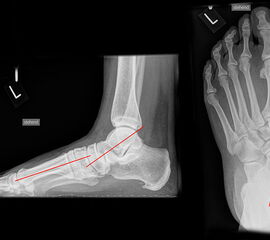

Röntgenaufnahmen des Fußes d.p., streng seitlich und schräg unter Belastung. Saltzmann Aufnahme zur Beurteilung der Rückfussachse.

Operationsplanung anhand der Röntgenaufnahmen unter Beachtung wichtiger radiologischer Landmarks wie Rückfussachse, Metatarsale I – Talushals-Achse im dp und lateralen Strahlengang (Abbildung 1 und 2).

Abbildung 1

Abbildung 2